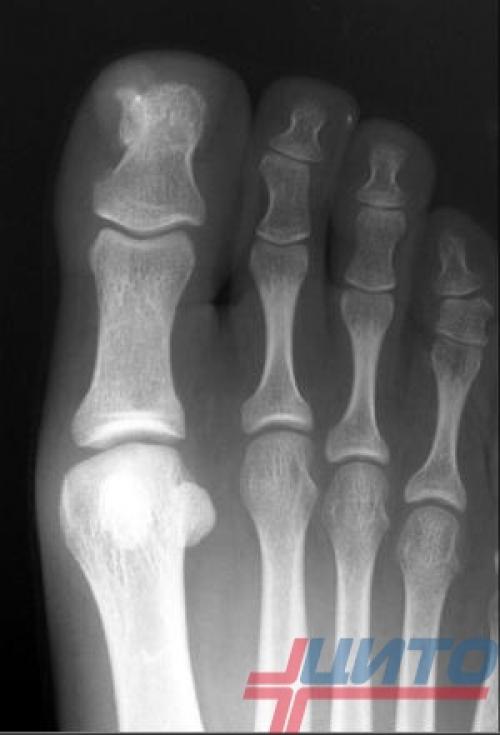

Ответ: Диагностика нароста на фаланге указательного пальца обычно проводится с помощью рентгенографии, которая позволяет оценить размер и местоположение нароста, а также степень повреждения окружающих тканей.

Экзостозы пальцев рук и ног могут представлять собой остеохондрому, т. е. доброкачественную опухоль, или быть следствием травмы, хронического воспалительного процесса или даже длительного ношения тесной обуви. Последние факторы чаще провоцируют образование экзостозов у взрослых.

Остеохондромы в основном типичны для детей и подростков до 20 лет. Они могут быть единичными или солитарными, а также множественными. Солитарные остеохондромы пальцев рук и ног – редкое явление. Чаще при наличии экзостозов с такой локализацией обнаруживаются аналогичные поражения других костей скелета, в частности бедренной, большеберцовой, плечевой, позвоночника, ключицы и т. д.